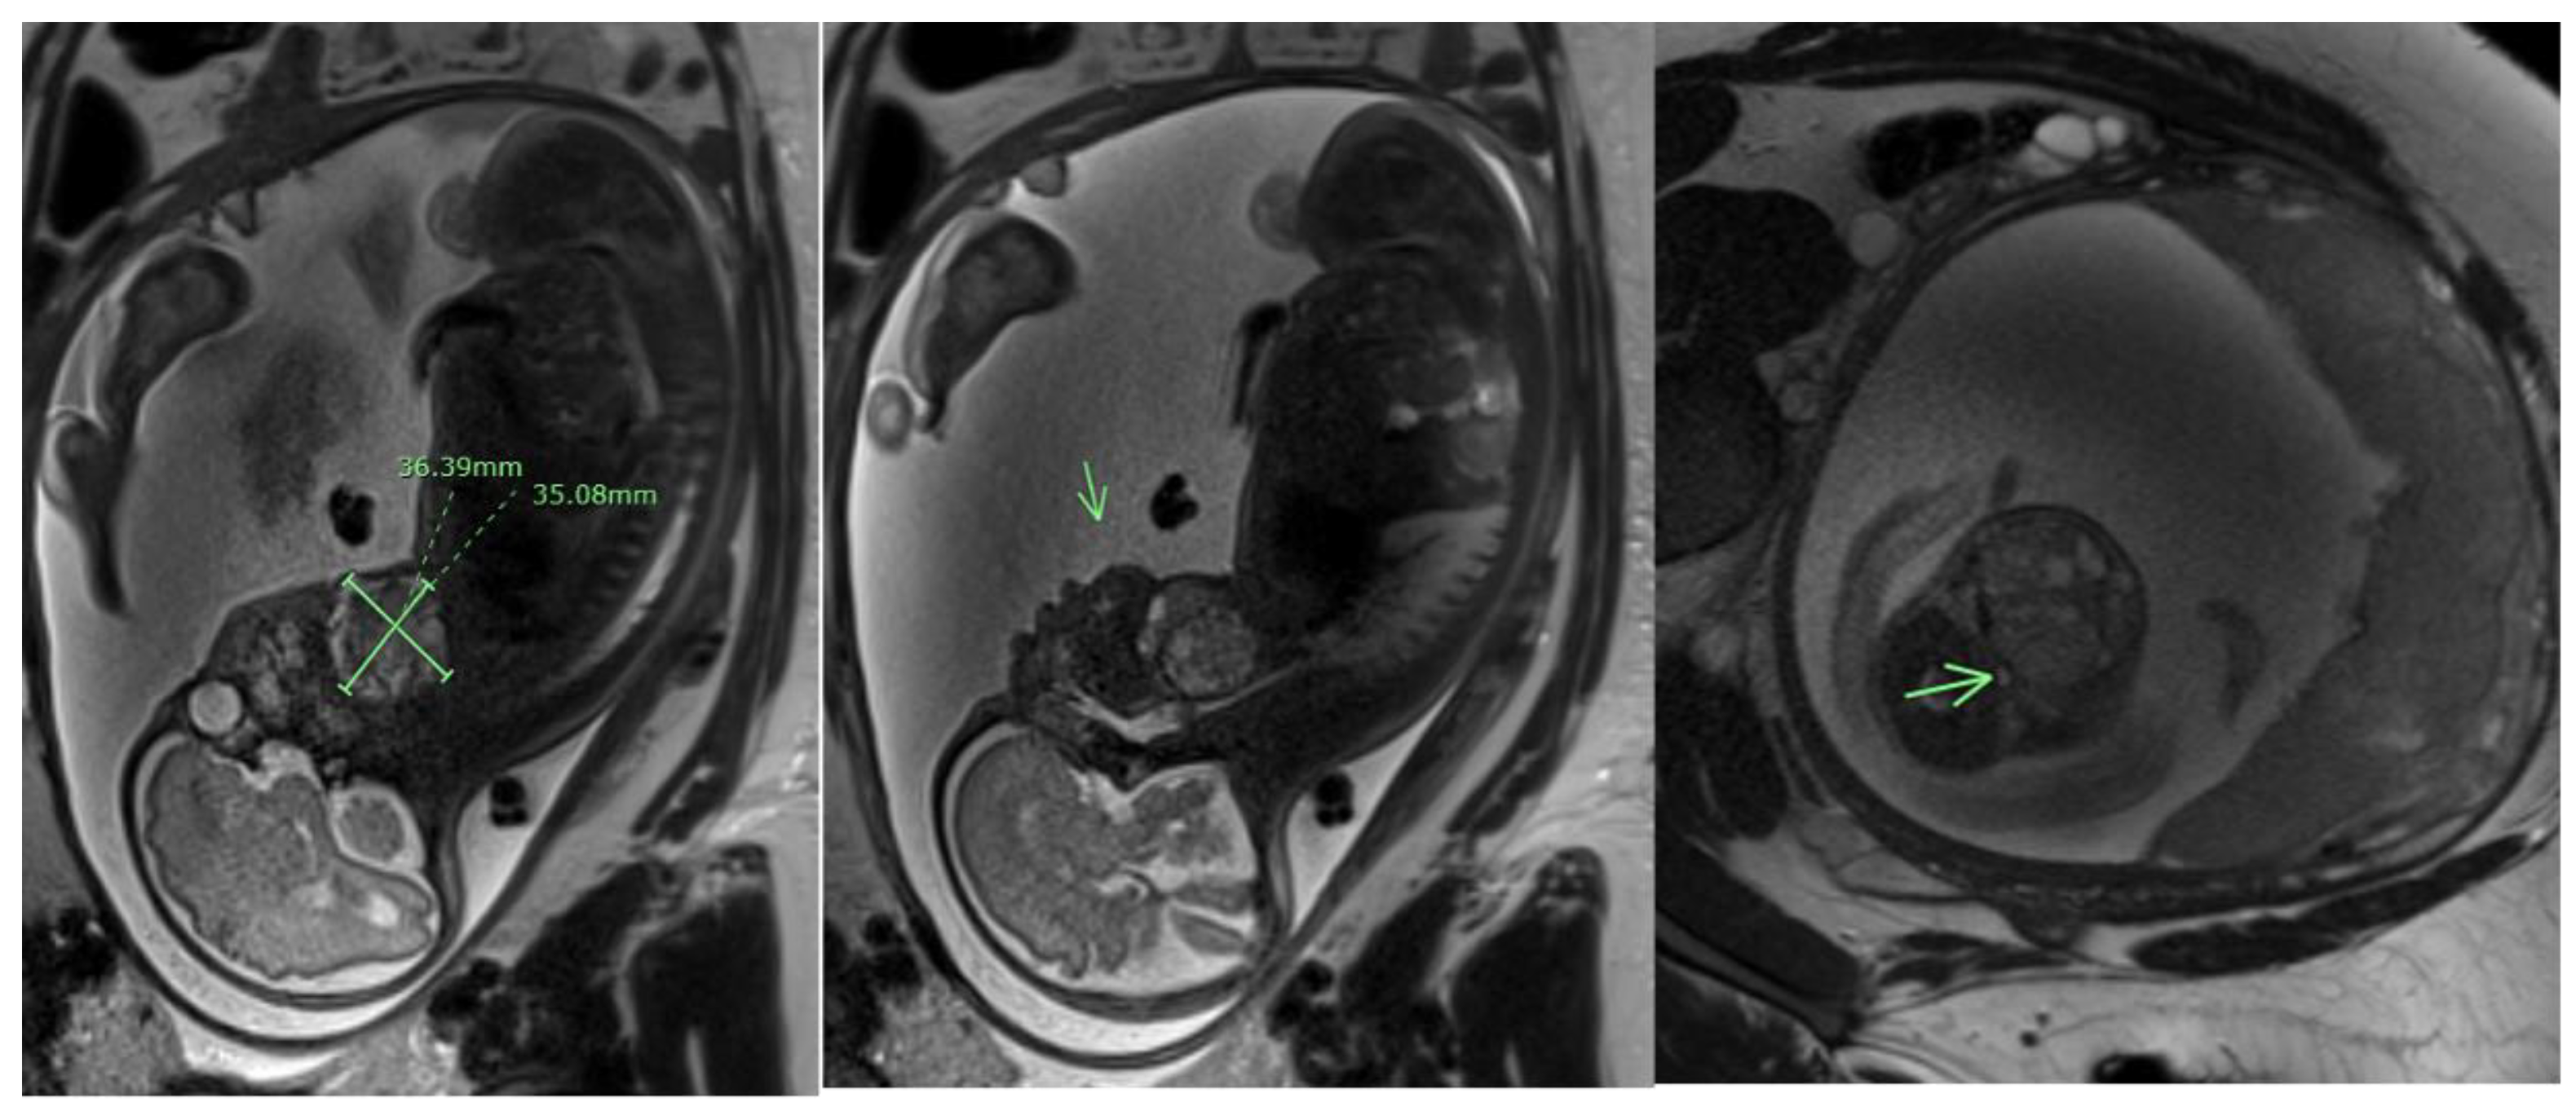

- Varlas, V.N.; Cloțea, E.M.; Varlas, R.G.; Pop, A.; Peneș, O.; Crețoiu, D.; Dima, V.; Bălănescu, L. Immature Sacrococcygeal Teratoma: A Case Report and Extensive Review of the Literature. Diagnostics 2024, 14, 246. [Google Scholar] [CrossRef] [PubMed]